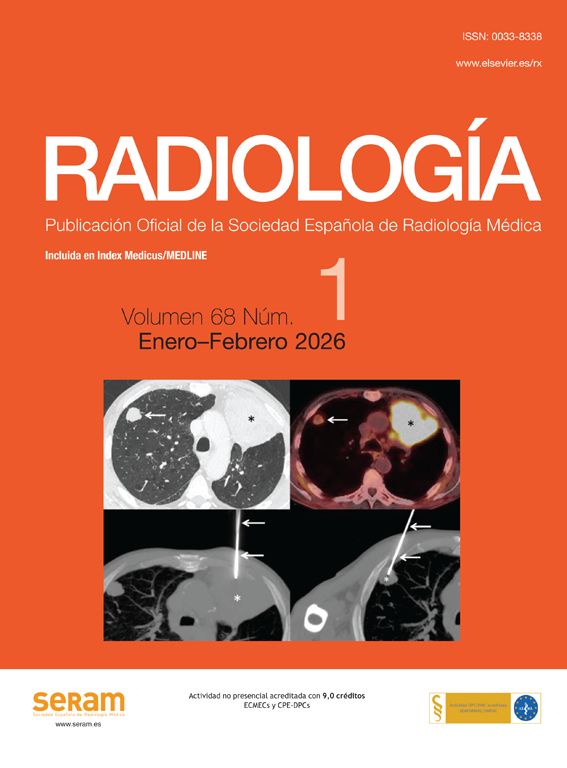

El plasma rico en plaquetas (PRP) es un preparado con fines terapéuticos cada vez más aceptado en diversas patologías musculoesqueléticas, debido a su teórico potencial para reparar tejidos con baja capacidad curativa. Se han realizado diversos ensayos clínicos aleatorizados que investigan la capacidad del PRP para la reparación de tendones, ligamentos, músculos y cartílago. Hasta la fecha existe evidencia 1A que apoya su uso para la epicondilitis lateral, la osteoartritis de rodilla, la fascitis plantar y tendinopatías del manguito rotador, y evidencia 1B en la tendinopatía del tendón rotuliano y la osteoartritis de cadera. Estudios retrospectivos, de cohortes y series de casos describen resultados prometedores del PRP para el tratamiento de otras patologías musculoesqueléticas.

Al ser sus efectos secundarios menores que los de los grupos controles hacen que sea un tratamiento considerado como prácticamente inocuo y cada vez más usado. Son necesarios nuevos ensayos clínicos aleatorizados para establecer futuras indicaciones y confirmar su efectividad y seguridad.

Platelet-rich plasma (PRP) is a preparation for therapeutic purposes that is increasingly accepted for various musculoskeletal disorders, due to its theoretical potential to repair tissues with poor healing capacity. Several randomised clinical trials have investigated the capacity of PRP to repair tendons, ligaments, muscles and cartilage, and to date there is level 1a evidence to support its use for lateral epicondylitis, osteoarthritis of the knee, plantar fasciitis and rotator cuff tendinopathy; and level 1b for patellar tendinopathy and osteoarthritis of the hip. Retrospective cohort studies and case series describe promising results with PRP for treating other musculoskeletal disorders.

Since its side effects are fewer than those of the control groups, the treatment is considered practically harmless and is being increasingly used. Further randomised clinical trials are necessary to establish future indications, and to confirm effectiveness and safety.

El plasma rico en plaquetas (PRP) es un preparado con fines terapéuticos cada vez más aceptado para el tratamiento de diversas patologías musculoesqueléticas debido a su teórico potencial para reparar tejidos con baja capacidad curativa1 y a su aparente inocuidad.

Desde sus comienzos en las décadas de 1980 y 1990 con sus aplicaciones en cirugía cardíaca y maxilofacial2, ha experimentado un gran auge en los últimos años debido a su uso en el mundo de la práctica deportiva de alto nivel para el tratamiento de lesiones tendinosas, musculares, ligamentosas y cartilaginosas1–3.

El PRP se define como una preparación de plasma con concentración de plaquetas mayor que la que se encuentra en el torrente sanguíneo de una persona sana (200.000 por microlitro)1,4,5 y que por lo general se ha definido como cinco veces mayor6. La función de las plaquetas es la de ser iniciadoras de la cascada inflamatoria que permita la presencia de factores de crecimiento tisulares que medien la reparación del tejido.

Revisaremos los fundamentos biológicos del PRP, sus aplicaciones en la patología musculoesquelética y sus evidencias actuales.